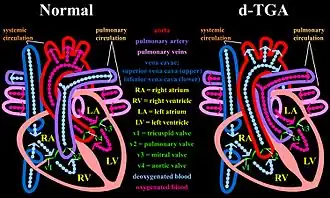

Dextro-Transposition of the great arteries (also known as dextro-TGA) is a cyanotic heart defect in which the aorta arises from the right ventricle and the pulmonary artery arises from the left ventricle. This switch causes deoxygenated blood from the right heart to be pumped immediately through the aorta and circulated throughout the body and the heart itself, bypassing the lungs altogether. In this same condition, the left heart continuously pumps oxygenated blood back into the lungs through the pulmonary artery, instead of out into the body's circulation as it normally would. In effect, two separate "parallel" circulatory systems are created. It is called a cyanotic congenital heart defect (CHD) because the newborn infant turns blue (cyanotic) from the lack of oxygen.

Levo-Transposition of the great arteries (also known as Levo-TGA, congenitally corrected TGA, double discordance, or ventricular inversion) is a rare, acyanotic heart defect in which the primary arteries are transposed, with the aorta anterior and to the left of the pulmonary artery, and the morphological left and right ventricles with their corresponding atrioventricular valves are also transposed.[3] In other words, the right ventricle is on the left side of the heart and the left ventricle is on the right side of the heart. The systemic and the pulmonary circulation are connected in this condition. Complications can arise from the pressure change due to the fact that the right ventricle, which is adapted for pumping blood into the low-pressure pulmonary circulation, is being tasked with pumping blood at a much higher pressure against the high resistance of the systemic circulation, since it is now in the position of where the left ventricle is typically located.

In many cases, TGV is accompanied by other heart defects, the most common type being intracardiac shunts such as atrial septal defect including patent foramen ovale, ventricular septal defect, and patent ductus arteriosus. Stenosis, or other defects, of valves and/or vessels may also be present.